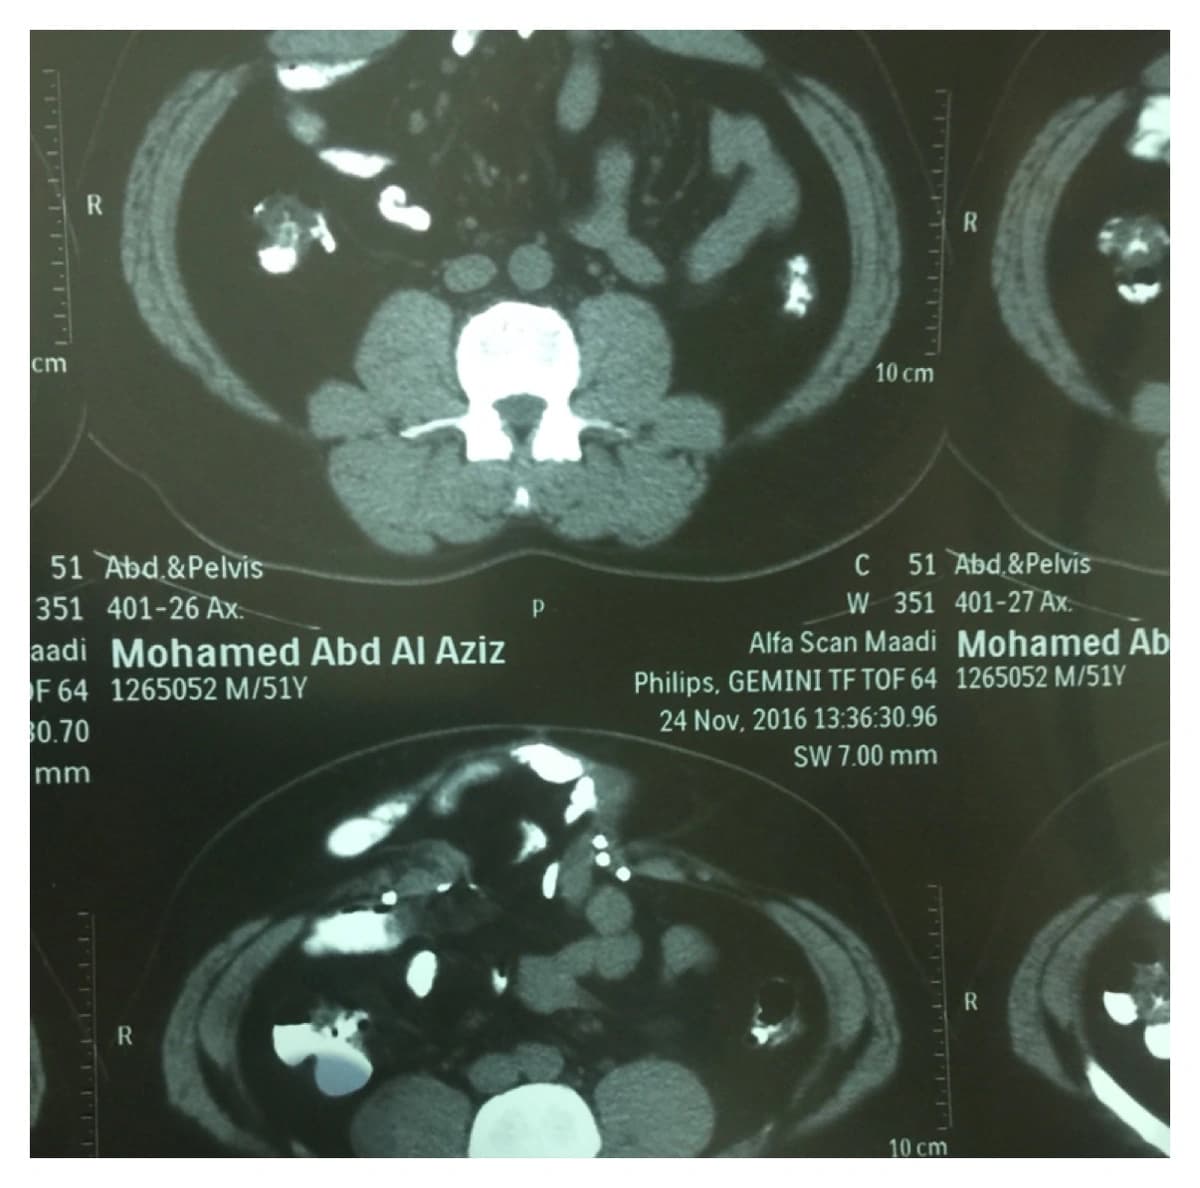

نجح فريق طبي بمستشفى الإمام عبدالرحمن الفيصل بمدينة الرياض، في إجراء عملية جراحية نادرة وشديدة الصعوبة، لمريض كاد أن يفقد حياته، بعدما رفضت عديد من المراكز الطبية في عدد من البلدان العربية إجراء الجراحة له لخطورتها. وقال الدكتور معتصم محمد إبراهيم، رئيس الفريق الطبي الذي أجرى الجراحة، إن المريض راجع المستشفى قبل فترة، حيث أجريت له فحوصات طبية شاملة، ووجد لديه "فتق" بعرض 10 سنتيمترات وطول 15 سنتيمترًا، إثر عملية سابقة، وتم تحديد الفتق بين الصرة وعظمة "القص".

وأضاف رئيس الفريق الطبي، أنه تمّت الموافقة على إجراء العملية بعد دراسة وضع المريض الصحي بشكل جيد، وبالصور المقطعية، وبحمد الله، أجريت العملية على ثلاث مراحل؛ الأولى تمثلت في إغلاق من داخل البطن؛ حيث وضعت شبكة جراحية مخصصة لذلك، وهي الخطوة التي اعتبرت كافية لإصلاح الفتق. ثم المرحلة الثانية، وكانت الأصعب، وهي فصل مكونات جدار البطن، ثم إعادة تشكيلها لإغلاق فتحة جدار البطن. وأخيرًا المرحلة الثالثة، وهي تثبيت جدار البطن من الخارج بوضع شبكة. مؤكدًا نجاح العملية وتماثل المريض للشفاء.